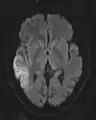

التصوير بالرنين المغناطيسي الموّزن بمعامل الانتشار "(Diffusion-weighted magnetic resonance imaging (DWI or DW-MRI" هي طريقة من التصوير التي تستخدم انتشار الماء في الحصول على تباين في صورة الرنين المغناطيسي.[1][2][3] [4][5][6]. تسمح لنا هذه الطريقة بإستخراج خريطة لعملية الانتشار للجزيئات، بشكل رئيسي الماء، في الأنسجة الحيوية، والكائنات الحية وليس العكس . الانتشار للجزيئات في الأنسجة ليس انتشاراً حُراً، ولكنه يعكس التفاعل مع الكثير من العقبات، مثل الجزيئات الضخمة، الألياف، والأغشية. أنماط انتشار جزيئات الماء قد تقودنا للكشف عن تفاصيل مجهرية تخص بناء النسيج، في حالة المرض أو الحالة الطبيعية للنسيج. وهناك أنواع خاصة من التصوير بالانتشار صورة مصفوفة الانتشار (diffusion tensor imaging (DTI أستخدمت على نطاق واسع لوضع خارطة لسير محاور الأعصاب في الدماغ وهذا ما يسمى ب white matter tractography in the brain.